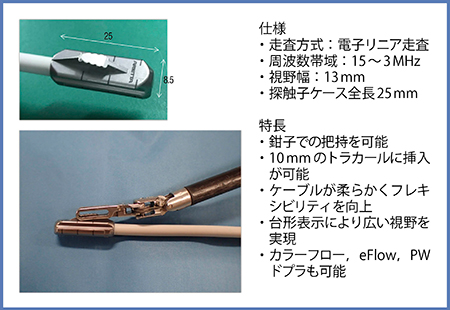

術中エコープローブは,腹腔鏡用として屈曲なしのリジッド型から前後左右4方向に屈曲するフレキシブル型へと進化し,2014年には日立製作所がドロップイン型プローブ「L43K」を発表した。L43Kには,(1) ロボットアームの鉗子で直接把持することで可動域を拡大し走査の自由度を高められる,(2) 接触面がフラットなリニアプローブのため凹凸のある臓器でも良好な画像が得られる,(3) プローブ背面に5mm間隔の目盛りがある,(4) ケーブルがしなやかで耐久性が高い,(5) 12mmのトラカールに挿入可能,(6) カラーフロー,eフロー,パワードプラ表示も可能,などの多くの特長がある。しかし,プローブ先端の長さが51mmと大きくケーブルがやや太いため,フレキシビリティの点で改善が望まれていた。

そこで,2016年に登場したのがL51Kである(図1)。L51Kは,L43Kの特長に加え,プローブ先端の長さが25mmと短く,幅も少し細くなり,ケーブルも細くなったため,10mmのトラカールへの挿入も可能である。

図1 小型化された術中エコープローブL51K